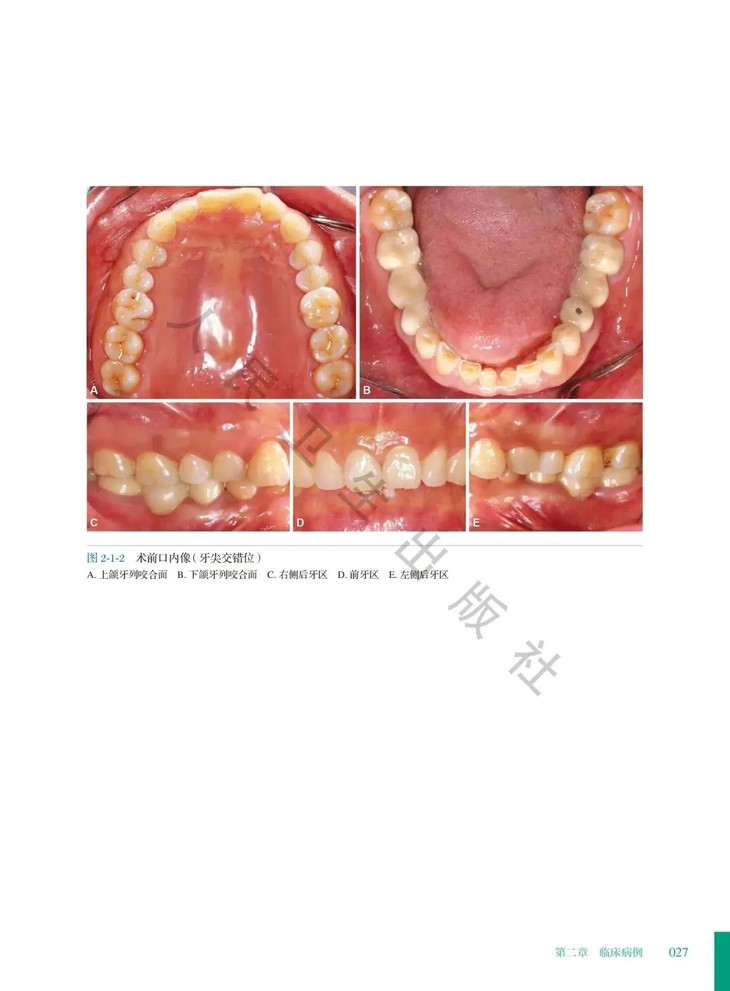

②. 本册收录短面型病例,临床最多见的是前牙磨损。这类病例具有共同的临床特征,可以详细说明治疗方法的共性;每个病例又针对患者各自的特点做了相应的调整,各有侧重。